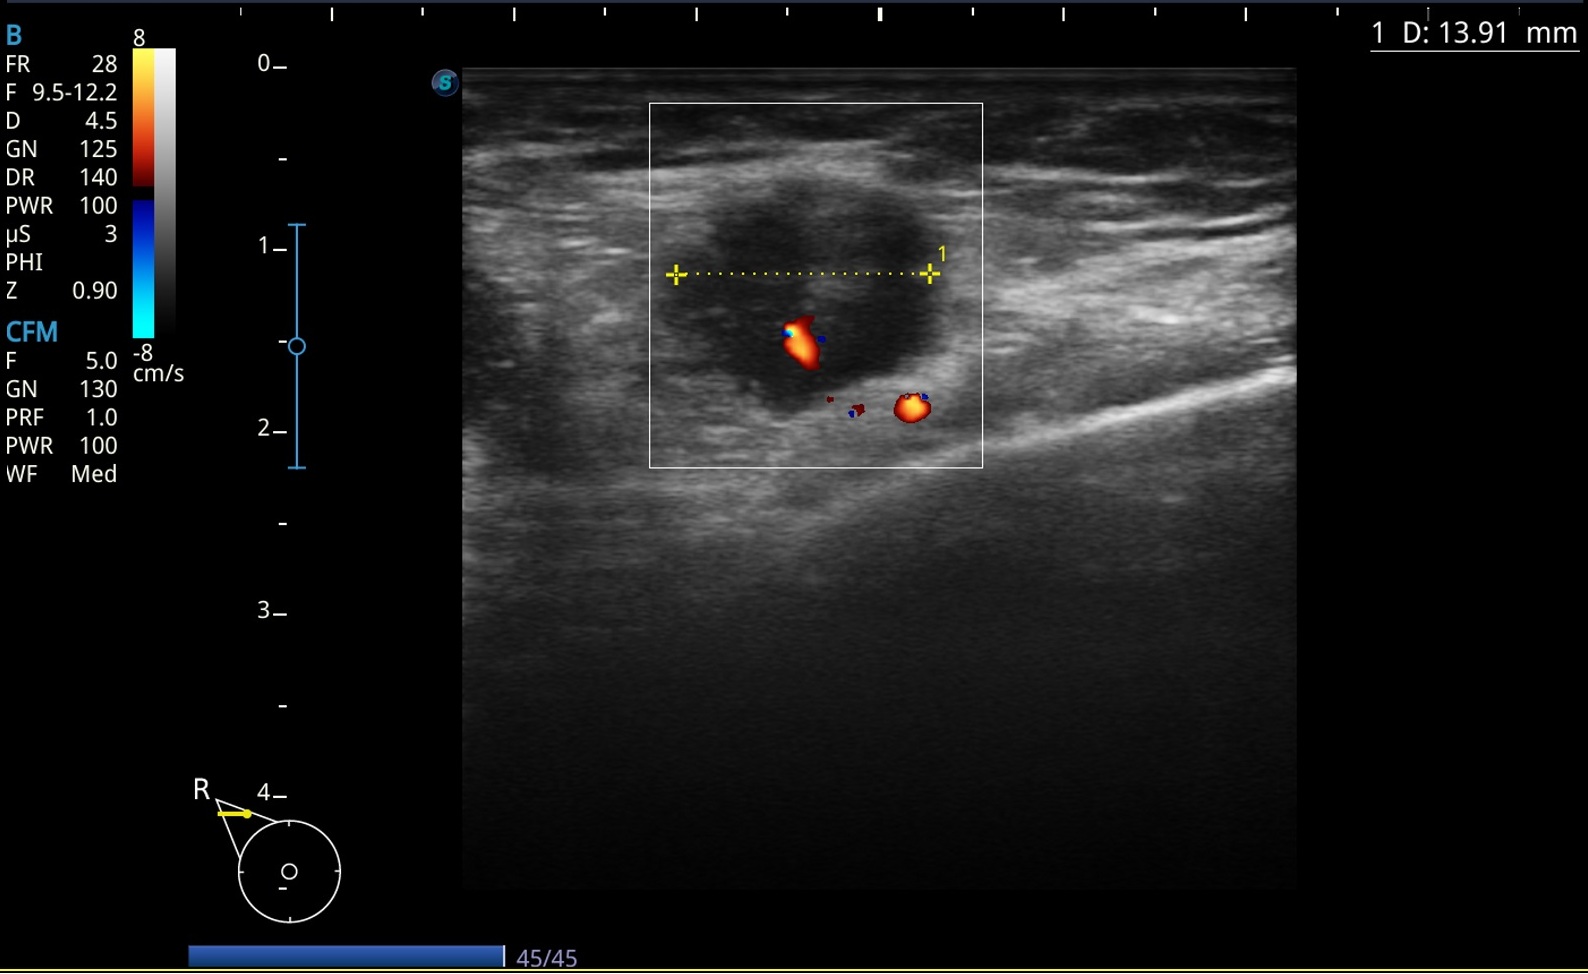

Adenopatía derecha redonda mal definida hipoecoica de 1,4 cm con vascularización central de aspecto patológico.